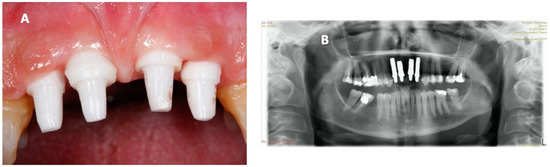

Hyperbaric Oxygen Therapy and A-PRF Pre-Treated Implants in Severe Periodontitis: A Case Report

2. Case Report